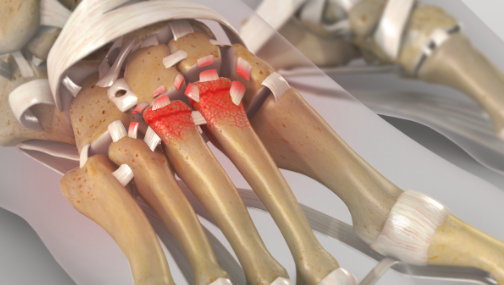

Joints are covered by articular cartilage which allows a bone to glide over another without symptoms. In the case of arthritis this covering is lost with the bones grinding and subsequent pain.

Investigations will enable us to confirm which joint or joints are arthritic. There are no joint replacements available for this area of the body. Given that the movement in this part of the foot is minimal, most patients fair well with fusion of the affected joints.